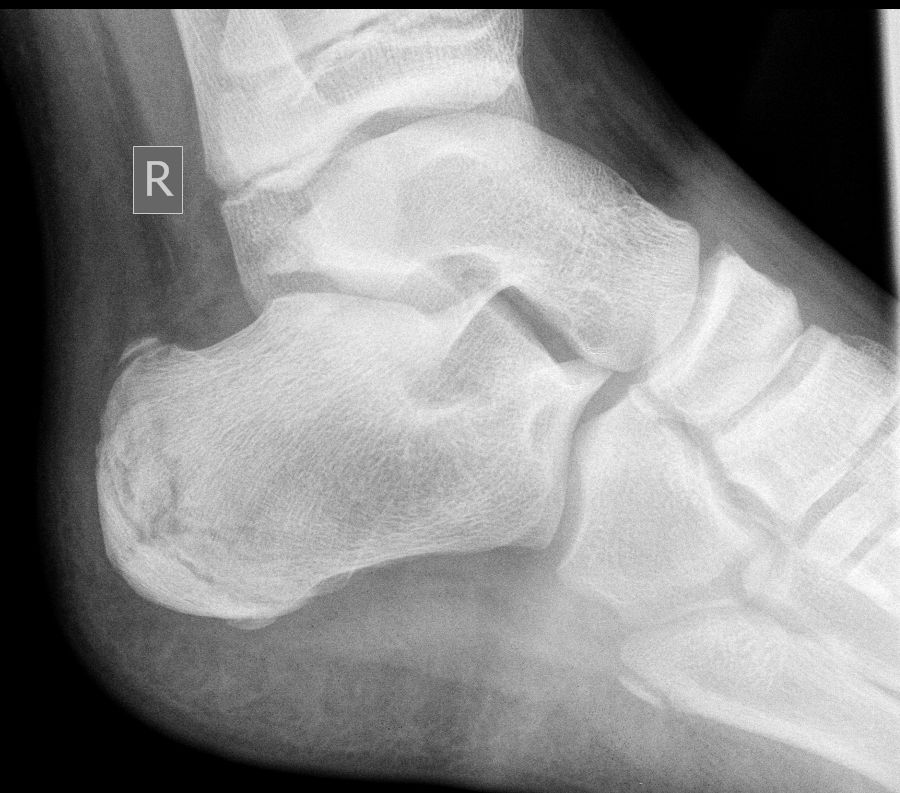

Давнишнее исследование. Уж 3 года как. Случай коллеги. Подросток, 15 или 16 лет. Болит пятка.

Хаглунда-Шинца болезнь (остеохондроз апофиза пяточной кости) - вариант остеохондропатии апофизов в бугре пяточной кости.

Рентгеновская диагностика. При болезни Шинца на снимке будет наблюдаться пятнистость паточной кости и отсутствие гомогенности тени ее бугра. В некоторых случаях возможно наличий отложения солей, которые видны как небольшие островки. При тяжелых формах заболевания отчетливо просматриваются такие рентгенологические признаки как отделение фрагментов краевой кости и увеличение расстояния между пяточной костью и апофизом.

Также стоит учесть, что для исключения множества других заболеваний (пяточная шпора, остеомиелит, туберкулез пяточной кости, периостит, ахиллобурсит и т.д.) необходимо проведение дифференциальной диагностики.

Снимки интересные, ничего не скажешь. Но топикстратер говорил о ребенке 10 лет. А в вашем случае, явный взрослый. Может, есть смысл о синдроме Хаглунда говорить в этом случае.

1. пятнистость и негомогеннность указывал Рейнберг ещё, но и про секвестроподобность оных писал( т.е. не просто пятнистость и гомогенность.)

2. островки отложения каких-то солей? Рейнбергом описано так, то что имеется в энтом апофизе несколько точек окостенения, числом до 3-4! И при этом они не имеют правильной формы и контуры не гладкие и м.б. и зазубренные!(т.е. всякие)

3.увеличение расстояния между пяточной костью и апофизом? Так вот дедушка пишет, что это разрастание!!!( не хондроз!или дегенерация) хряща.

4. По поводу приведенных снимков: очень интересная картина АХИЛЛОБУРСИТА+ пяточного бурсита (. Т.е. требует дифф. диагностики... )

5. Коллега, Андрей Юрьевич, справедливо заметил, что приведенные снимки скорее относятся к деформации или болезни Хаглунда. http://www.travmaorto.ru/139.html а не к б-ни Шинца.

А на счет 5 пункта...Болезнь Хаглунда или как ее еще называют – деформация Хаглунда – является разновидностью остеохондропатий. Выражается она в костном наросте экзостозе. Этот нарост внешне похож на шишку, место возникновения которой - задняя часть пяточной кости, немного выше места, куда крепится ахиллово сухожилие. По мере увеличения нарост начинает давить на ахиллово сухожилие и сумку из-за чего возникает ретрокалканеальный бурсит (воспаление сумки) и тендинит (воспаление сухожилия)...и т.д.